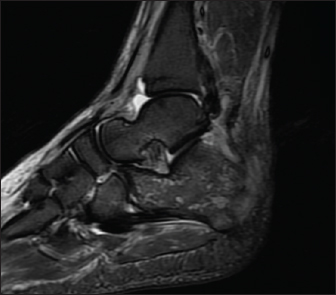

A 70-year-old male known to have diabetes mellitus presented with a 1 month history of fever and weight loss. History of multiple hospital visits and several courses of oral and intravenous antibiotics were present. Physical examination revealed hepatosplenomegaly. As he was fitting the criteria for Pyrexia of Unknown origin, work for the same was done. Routine investigations showed neutrophilic leucocytosis with raised inflammatory markers. Widal was negative. Ultrasound abdomen showed features of chronic liver disease. Contrast CT scan of abdomen showed splenic infarcts. He was started on antibiotics, but he had ongoing fever spikes. While in hospital he developed difficulty in walking due to left ankle pain. MRI foot (Fig. 1) was taken showed small intraosseous abscess in calcaneal bone. Blood cultures grew B. pseudomallei. The patient had a good recovery and was followed up in the outpatient clinic ray foot (Fig. 2) was repeated showed a resolution of osteomyelitis.

Fig. 2. Xray Rt foot after 3 months of treatment—patient 1.